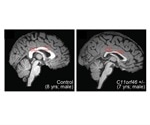

Epigenome editing could repair genetic brain disorder